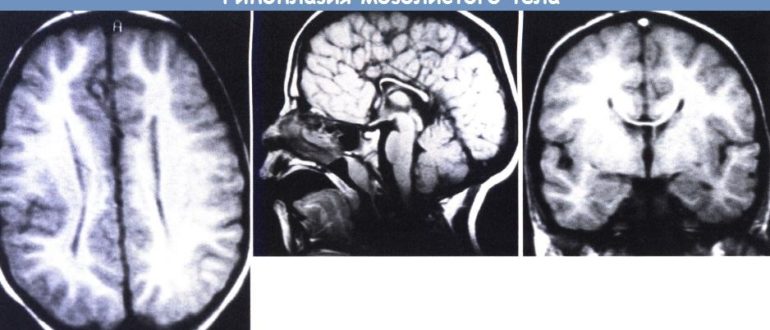

ВПР ЦНС: сужение полости прозрачной перегородки, гипоплазия мозолистого тела

Мозолистое тело головного мозга — агенезия прозрачной перегородки, гипоплазия у ребенка Агенезией мозолистого тела называют врожденную патологию мозга, причиной возникновения которой в большинстве случаев является генетический фактор, развивается…